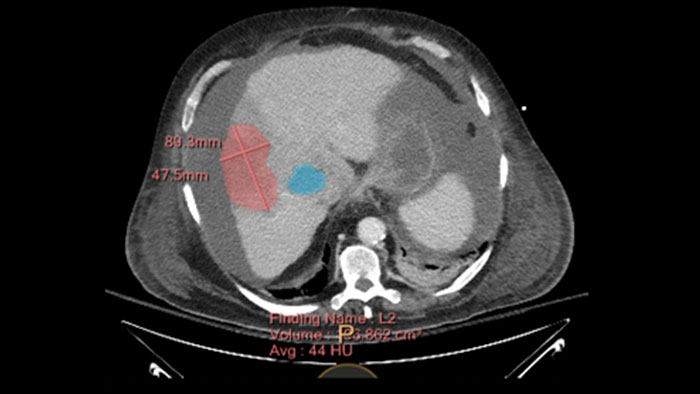

Multi Modality Tumor Tracking (MMTT)

MMTT is a post processing software used to display, process, analyze and quantify anatomical and functional images, for CT, MR, PET/CT, SPECT/CT and Dual Energy CT at one or multiple time points.

Benefits

• Enhanced semi-automatic volumetric segmentation.

• Selectable oncology response criteria including standards such as RECIST 1.0, RECIST 1.1, WHO, CHOI, PERCIST, irRC and mRECIST, as well as PET SUV analysis including glucose-corrected SUV.

• Findings can be shared with other IntelliSpace Portal applications such as CT Liver Analysis and CT Viewer or exported in different formats including RT Structures.